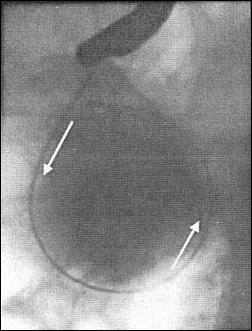

The diagnostic method prior to endoscopic drainage includes the clinical examination, laboratory findings, abdominal sonography, computed tomography (CT), magnetic resonance imaging(MRI) and endoscopic retrograde cholangiopancreatography(ERCP). Most of the pseudocysts were detected by means of sonography. The mean size of the cysts was 8,9 cm (range 6-21 cm) (Fig.1).

Fig. 1. CT scan showing the large pancreatic pseudocyst

(21 cm)